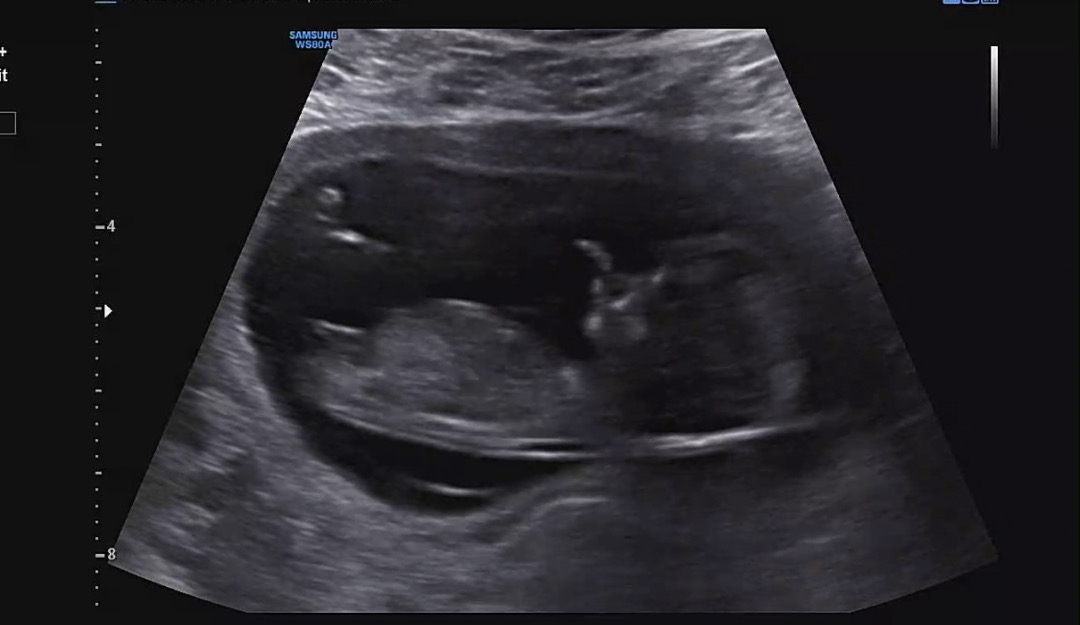

12주 각도법 부탁드려요💗

넘넘 궁금해요!!

딸같아요 ㅎㅎ